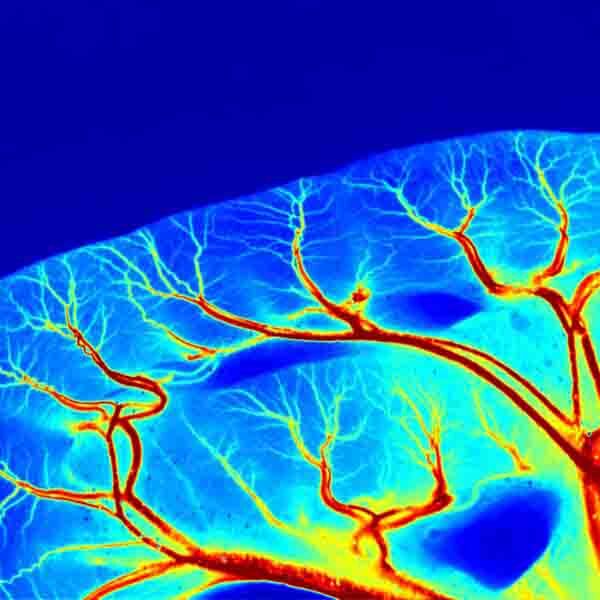

Визуализация in-vivo в ближнем ИК2 (NIR-2) диапазоне

Визуализация in-vivo в ближнем ИК2 (NIR-2) диапазоне